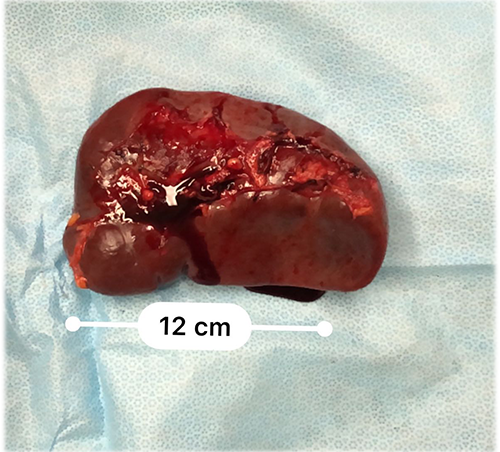

门脉高压、右肝动脉门静脉瘘、胆囊结石----脾切除、贲门周围血管离断、肝右动脉结扎、胆囊切除